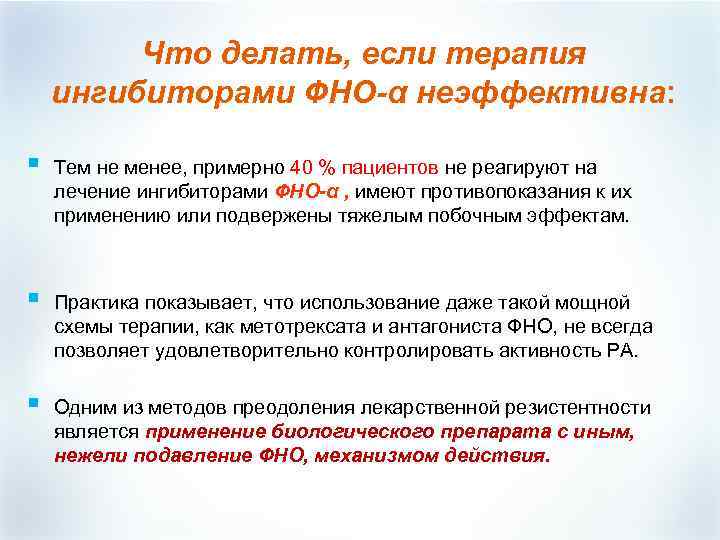

Что делать, если терапия ингибиторами ФНО-α неэффективна: § Тем не менее, примерно 40 % пациентов не реагируют на лечение ингибиторами ФНО-α , имеют противопоказания к их применению или подвержены тяжелым побочным эффектам. § Практика показывает, что использование даже такой мощной схемы терапии, как метотрексата и антагониста ФНО, не всегда позволяет удовлетворительно контролировать активность РА. § Одним из методов преодоления лекарственной резистентности является применение биологического препарата с иным, нежели подавление ФНО, механизмом действия.

Что делать, если терапия ингибиторами ФНО-α неэффективна: § Тем не менее, примерно 40 % пациентов не реагируют на лечение ингибиторами ФНО-α , имеют противопоказания к их применению или подвержены тяжелым побочным эффектам. § Практика показывает, что использование даже такой мощной схемы терапии, как метотрексата и антагониста ФНО, не всегда позволяет удовлетворительно контролировать активность РА. § Одним из методов преодоления лекарственной резистентности является применение биологического препарата с иным, нежели подавление ФНО, механизмом действия.